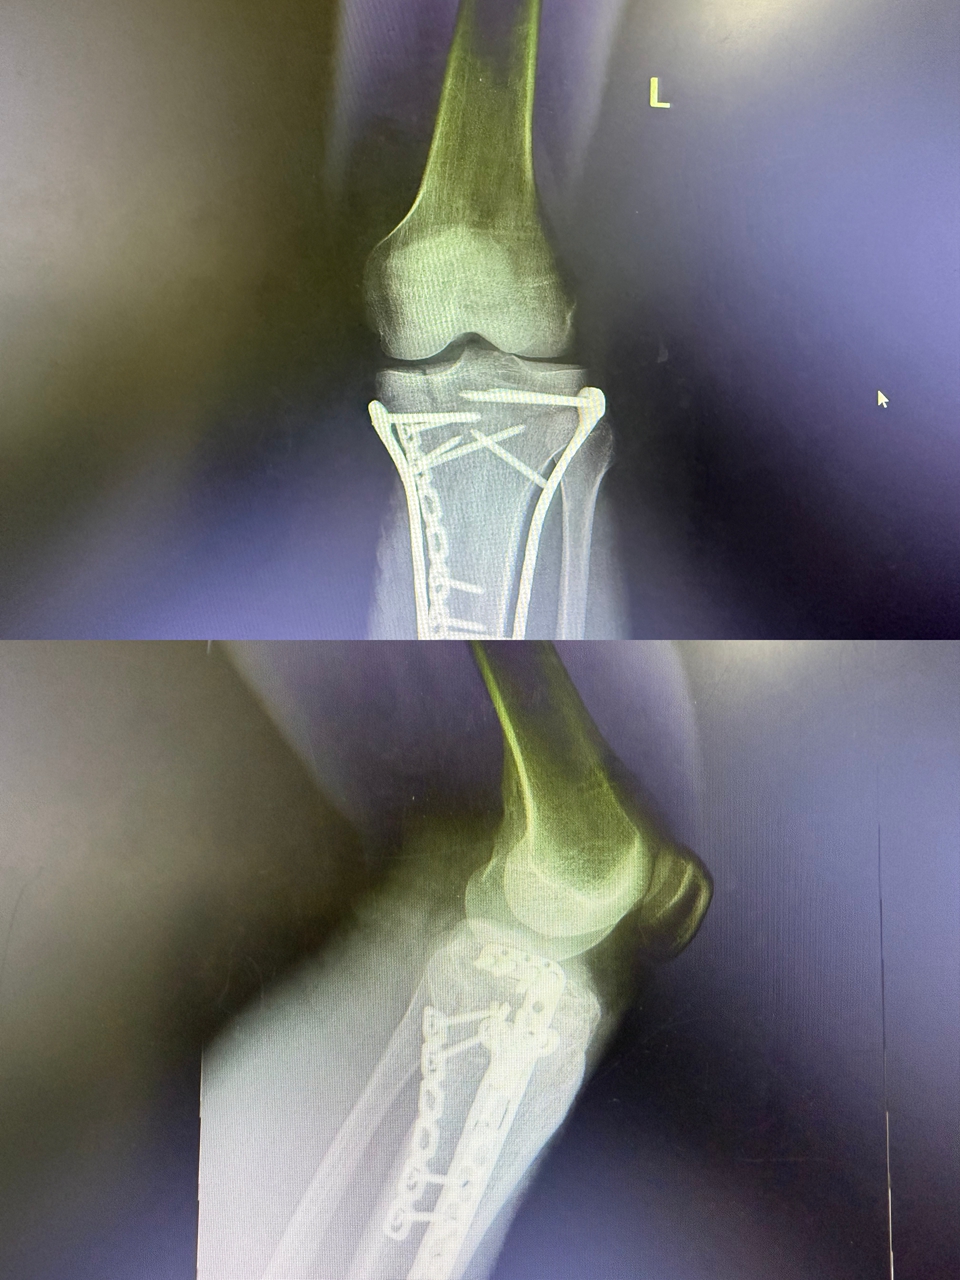

术后复查X片提示骨折端对位对线良好,关节面平整,下肢力线恢复正常